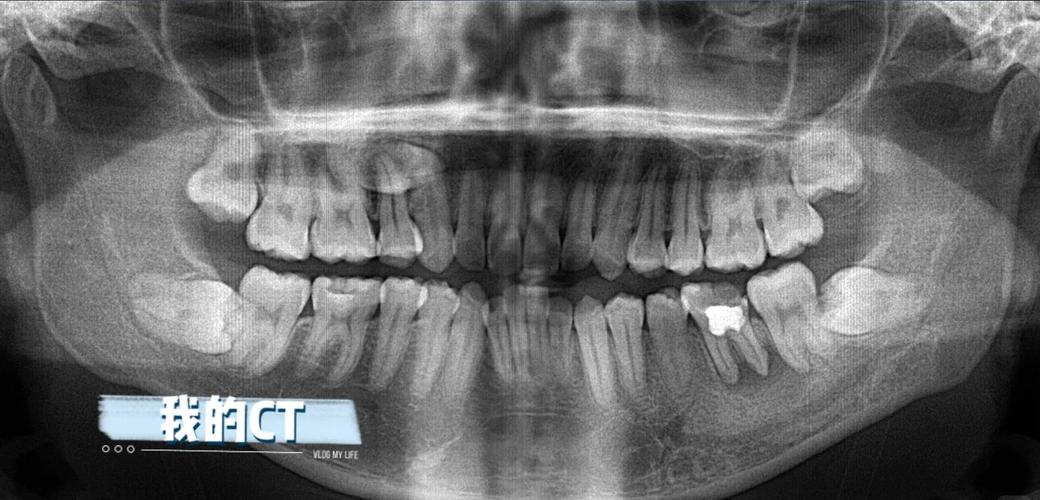

CBCT(锥形束CT)是近年来广泛应用于复杂正畸病例的三维影像检查,相比传统CT,CBCT辐射剂量更低(约为传统CT的1/10),且能获取高分辨率的三维图像,清晰展示牙齿、牙根、牙槽骨、颌骨及神经血管的三维空间关系,CBCT的适应症包括:复杂牙列拥挤或牙量骨量不匹配时,评估埋伏牙(如多生牙、阻生尖牙)的位置、萌出方向及与邻牙的关系;种植支抗植入前,观察牙槽骨的厚度、高度及重要解剖结构(如上颌窦、下牙槽神经管)的位置;正畸治疗中评估牙根吸收情况;以及需要正畸正颌联合治疗时,精确测量颌骨的三维数据,需要注意的是,CBCT并非所有正畸患者的必需检查,医生会根据病情需要决定是否拍摄,以避免不必要的辐射。

| CBCT | 三维展示牙齿、牙根、牙槽骨及神经血管关系,精确评估复杂解剖结构 | 复杂牙列拥挤、埋伏牙、种植支抗、正畸正颌联合治疗 | 辐射剂量高于普通片子,需严格掌握适应症 |